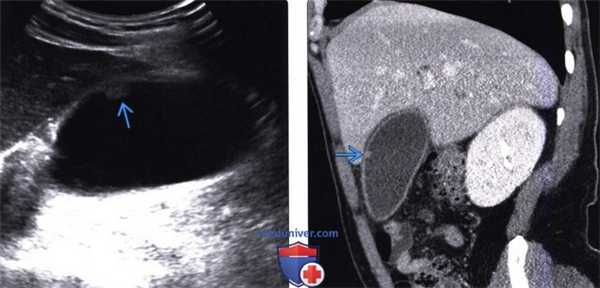

(Левый) Положение пациента на левом боку. На продольном УЗ срезе визуализируется холестериновый полип; стенка желчного пузыря не изменена.

(Правый) Тот же пациент. Некоторое время спустя выполнена КТ с контрастным усилением. На сагиттальной томограмме определяется холестериновый полип, отмечается легкое неспецифическое утолщение стенки желчного пузыря.